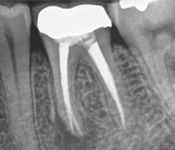

Pictured: Preoperative and Postoperative

Our patient presented with severe pain and required emergency root canal treatment. After cleaning and removing the inflamed pulp, the root canal system was successfully restored and the natural tooth saved.